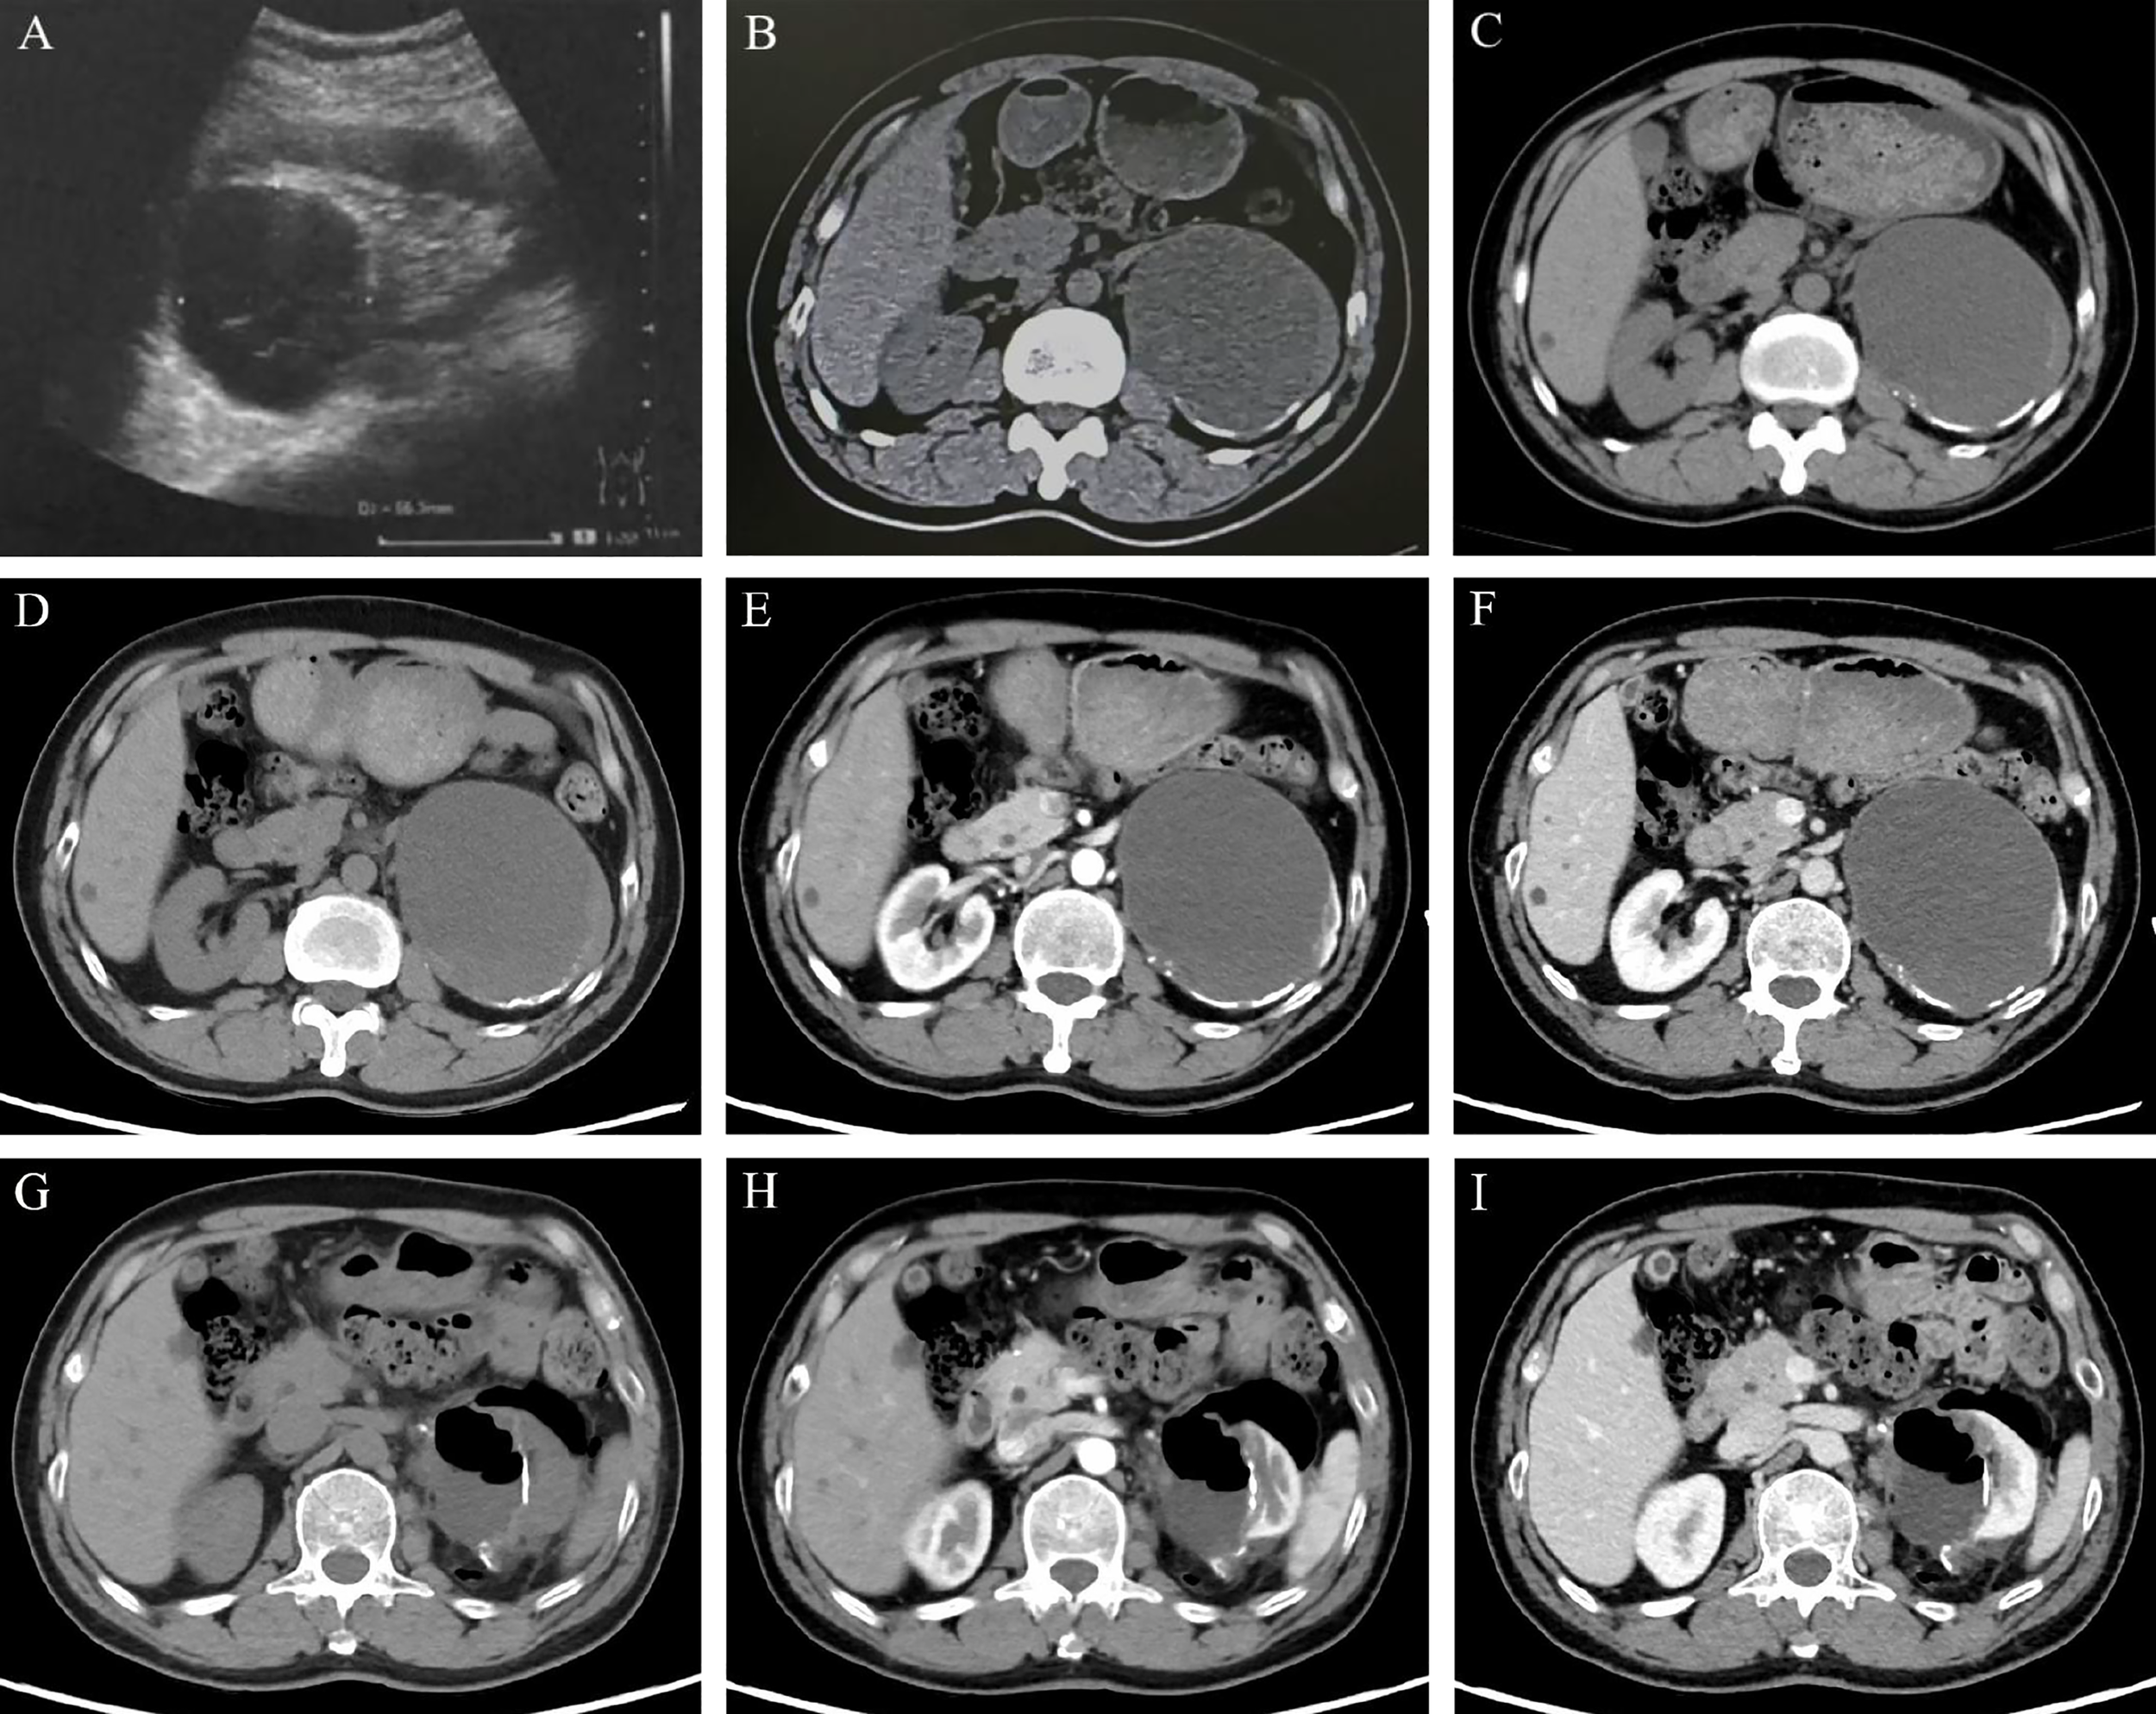

A 55-year-old man presented with a large cystic mass of the left kidney without any subjective discomfort. Fifteen years before admission, he was diagnosed with a left renal cyst and subsequently underwent three paracenteses combined with anhydrous alcohol sclerotherapy. Thereafter, he received regular color Doppler ultrasound or computed tomography (CT) examinations. The objective data showed the cystic lesion measuring 6.4 × 5.5 cm in 2013, 9.5 × 7.6 cm in 2017, and 10.0 × 8.2 cm in 2019 with partial cyst wall calcification (Figures 1A–C). He had a medical history of blood transfusion due to gastric perforation 31 years earlier and a 13-year history of multiple hepatic cysts. Physical examination and routine blood tests revealed no abnormalities.

Imaging features of the left renal lesion. (A. February 28, 2013) Ultrasound revealed the cystic echogenic mass measuring 6.4 × 5.5 cm. (B. April 1, 2017) CT scan showed the cystic lesion of 9.5 × 7.6 × 6.7 cm. (C. October 22, 2019) CT scan showed the cystic lesion of 10.0 × 8.2 cm in cross-section with partial cyst wall calcification. Dynamic contrast-enhanced CT was performed to show the features of the lesion in UP (D, G), CMP (E, H), and NP (F, I). (D–F on May 28, 2020) A mixed-density mass dominated by low density was found in the left kidney, with a cross-section of 10.3 × 8.5 cm and multiple high-density patches at the edge. (G–I on June 15, 2020) With localized encapsulated gas and effusion, the left kidney was partially absent accompanied by marginal densification. Abbreviations: UP, unenhanced phase; CMP, corticomedullary phase; NP, nephrographic phase.

An admission dynamic contrast-enhanced CT revealed a mixed-density mass dominated by low density in the left kidney, measuring 10.3 × 8.5 cm in cross-section, with multiple high-density patches at the rim (Figures 1D-F, eFigure 1). No distinct change in mass density was found during the phase of enhancement, and the imaging impression was a complex cyst (Bosniak classification grade IIF) (9). Laparoscopic partial nephrectomy (PN) of the left kidney was then performed. Intraoperative inspection revealed the cystic mass occupying the upper pole of the left kidney, with an uneven surface and adhesion to surrounding fat. When a minor incision of about 0.5 cm was made, a large quantity of jelly-like mucus and bean-curd-like necrotic tissue was found filling the lesion. On gross specimen examination, the removed cystoid tissue was approximately 9.2 × 6.2 × 1.8 cm in size and 0.2 × 0.9 cm in wall thickness, with a smooth outer wall and a rough inner wall. Microscopically, extensive mucus was found in the fibrocyst wall, and the tumor cells were scattered or glandular in arrangement (Figure 2A). A pathological diagnosis of mucinous adenocarcinoma was presented. Immunohistochemistry (IHC) demonstrated that the tumor cells were positive for PCK, Villin, CDX2, SATB2 (some cells), Syn (a few cells), and Ki67 (50%) but negative for CgA, Napsin A, TTF-1, GATA-3, CK7, PAX-8, CA9, RCC, and P63. (Figures 2C–H, eFigure 2).

The patient underwent further general examination. Painless gastroscopy and colonoscopy revealed no abnormal lesions, while the carbohydrate antigen 19-9 (CA19-9), carbohydrate antigen 72-4 (CA72-4), and carcinoembryonic antigen (CEA) indexes were elevated (79.20 U/ml, 50.10 U/ml, 5.24 ng/ml, respectively). A CT scan of the head and chest showed no evidence of metastasis, and a repeated abdominal CT scan revealed a localized encapsulation of gas and effusion (Figures 1G–I).